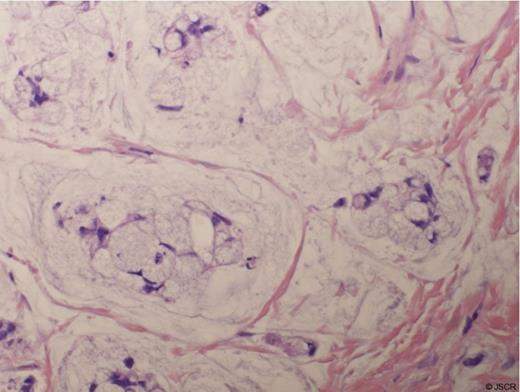

The patient underwent urethral diverticulectomy, during which 2 separate diverticula were noted, one at 5 and one at 7 o’clock. Intra-operative frozen section revealed fibrotic tissue. Final pathology, however, revealed invasive high grade adenocarcinoma involving both diverticula with signet ring cell features and mucin production, see Figure 2.

H&E Stain of the Signet Ring Adenocarcinoma from the Urethral Diverticulum

The patient underwent a robotic assisted radical cystectomy, bilateral pelvic lymph node dissection, and ileal conduit urinary diversion. The dissection was taken down as wide as possible, to the farthest reaches of the lateral fornix of the vagina and to the inferior ramus of the pubic bone bilaterally for a wide excision. Final pathology revealed invasive adenocarcinoma, 3.2 cm, surrounding the urethra and invading into the peri-urethral soft tissues, bladder, and vaginal wall with negative margins and lymph nodes. The tumor was composed of well-formed glands containing abundant mucin and signet ring cells.

Adenocarcinoma of the female urethra comprises only 10% of all primary urethral malignancies in women and is hypothesized to originate from Skene’s glands, paraurethral ducts, or glandular metaplasia of the urothelium (3). This is in direct contrast to the most common primary carcinoma of the female urethra, squamous cell carcinoma. Adenocarcinoma can be divided into mucinous and clear cell subtypes (4). The characteristic “signet ring” appearance occurs when abundant mucin accumulates in the cytoplasm of a cell and compresses the nucleus giving the appearance of a “signet ring”.